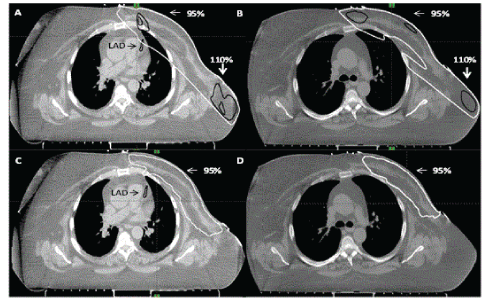

Results

In 3D CRT, 95% of PTV50_eval could be covered by 95% dose with hotspots of dose up to 115%. PTV40 could not be adequately covered because of excessive doses to the heart and lung. VMAT achieved planning objectives on target volumes and organs-atrisk. Fluoroscopy revealed minimal chest wall motion. Slice by slice examination of fused breath hold scan to free breathing scan revealed ≤ 5 mm chest wall motion. The heart and LAD moved away from the chest wall on deep inspiration (Figures 1 and 2). Comparison of the four techniques is shown in Table 2.